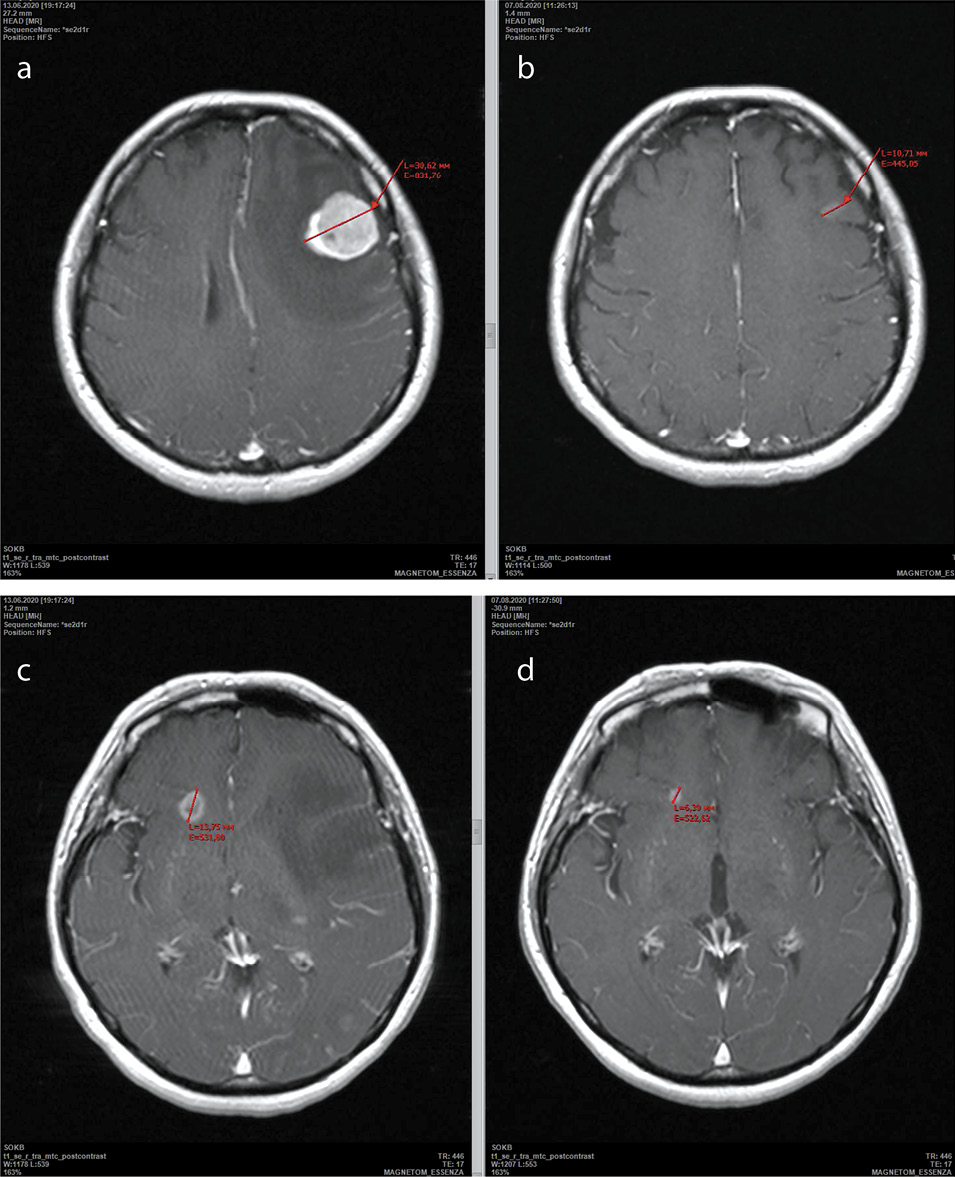

В представленном нами выше клиническом примере 4 (табл. 1) у пациентки полный ответ в головном мозге был отмечен уже на первом контроле – спустя 3 мес после начала терапии и сохранялся в течение всего периода наблюдения – более 24 мес (ответ сохранялся на момент написания статьи). Здесь на себя обращает внимание и возраст пациентки – 73 года.

В клиническом примере 1 у пациентки исходно имелись симптомные метастазы в головной мозг. Также на первом контроле неврологические симптомы исчезли, был достигнут частичный ответ (как экстра-, так и интракраниальный; рис. 4). Пациентка продолжала лечение на протяжении 15 мес. Терапия была прервана в связи с установленной новой коронавирусной инфекцией, осложненной двусторонней пневмонией с тяжелым течением, и последующей гибелью пациентки.

Рис. 4. Пациент 1. Магнитно-резонансная томография: a, c – до начала терапии осимертинибом; b, d – через 2 мес.

Fig. 4. Patient 1. Magnetic resonance imaging: a, c – the beginning of osimertinib therapy; b, d – 2 months after.